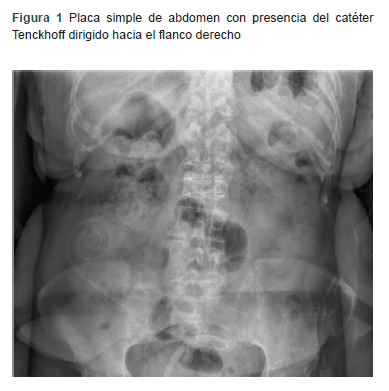

Clinical case: 64-year-old female patient presented with Tenckhoff catheter dysfunction. She was scheduled for catheter removal and placement. During the start of the infusion of dialysis solution, the patient started to feel the urgent need to urinate. A simple abdominal tomography was requested, confirming the catheter in the bladder.